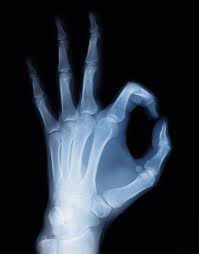

류마티스 관절염은 전형적으로 초기부터 손가락, 손목, 발가락 관절 등이 주로 침범되며, 병이 진행함에 따라 팔꿈치관절, 어깨관절, 발목관절, 무릎관절 등도 침범된다. 이러한 관절에 통증, 뻣뻣함, 종창(염증이나 종양 등으로 인하여 부어 오른 것) 등의 증상이 수 주에 걸쳐 서서히 나타난다.